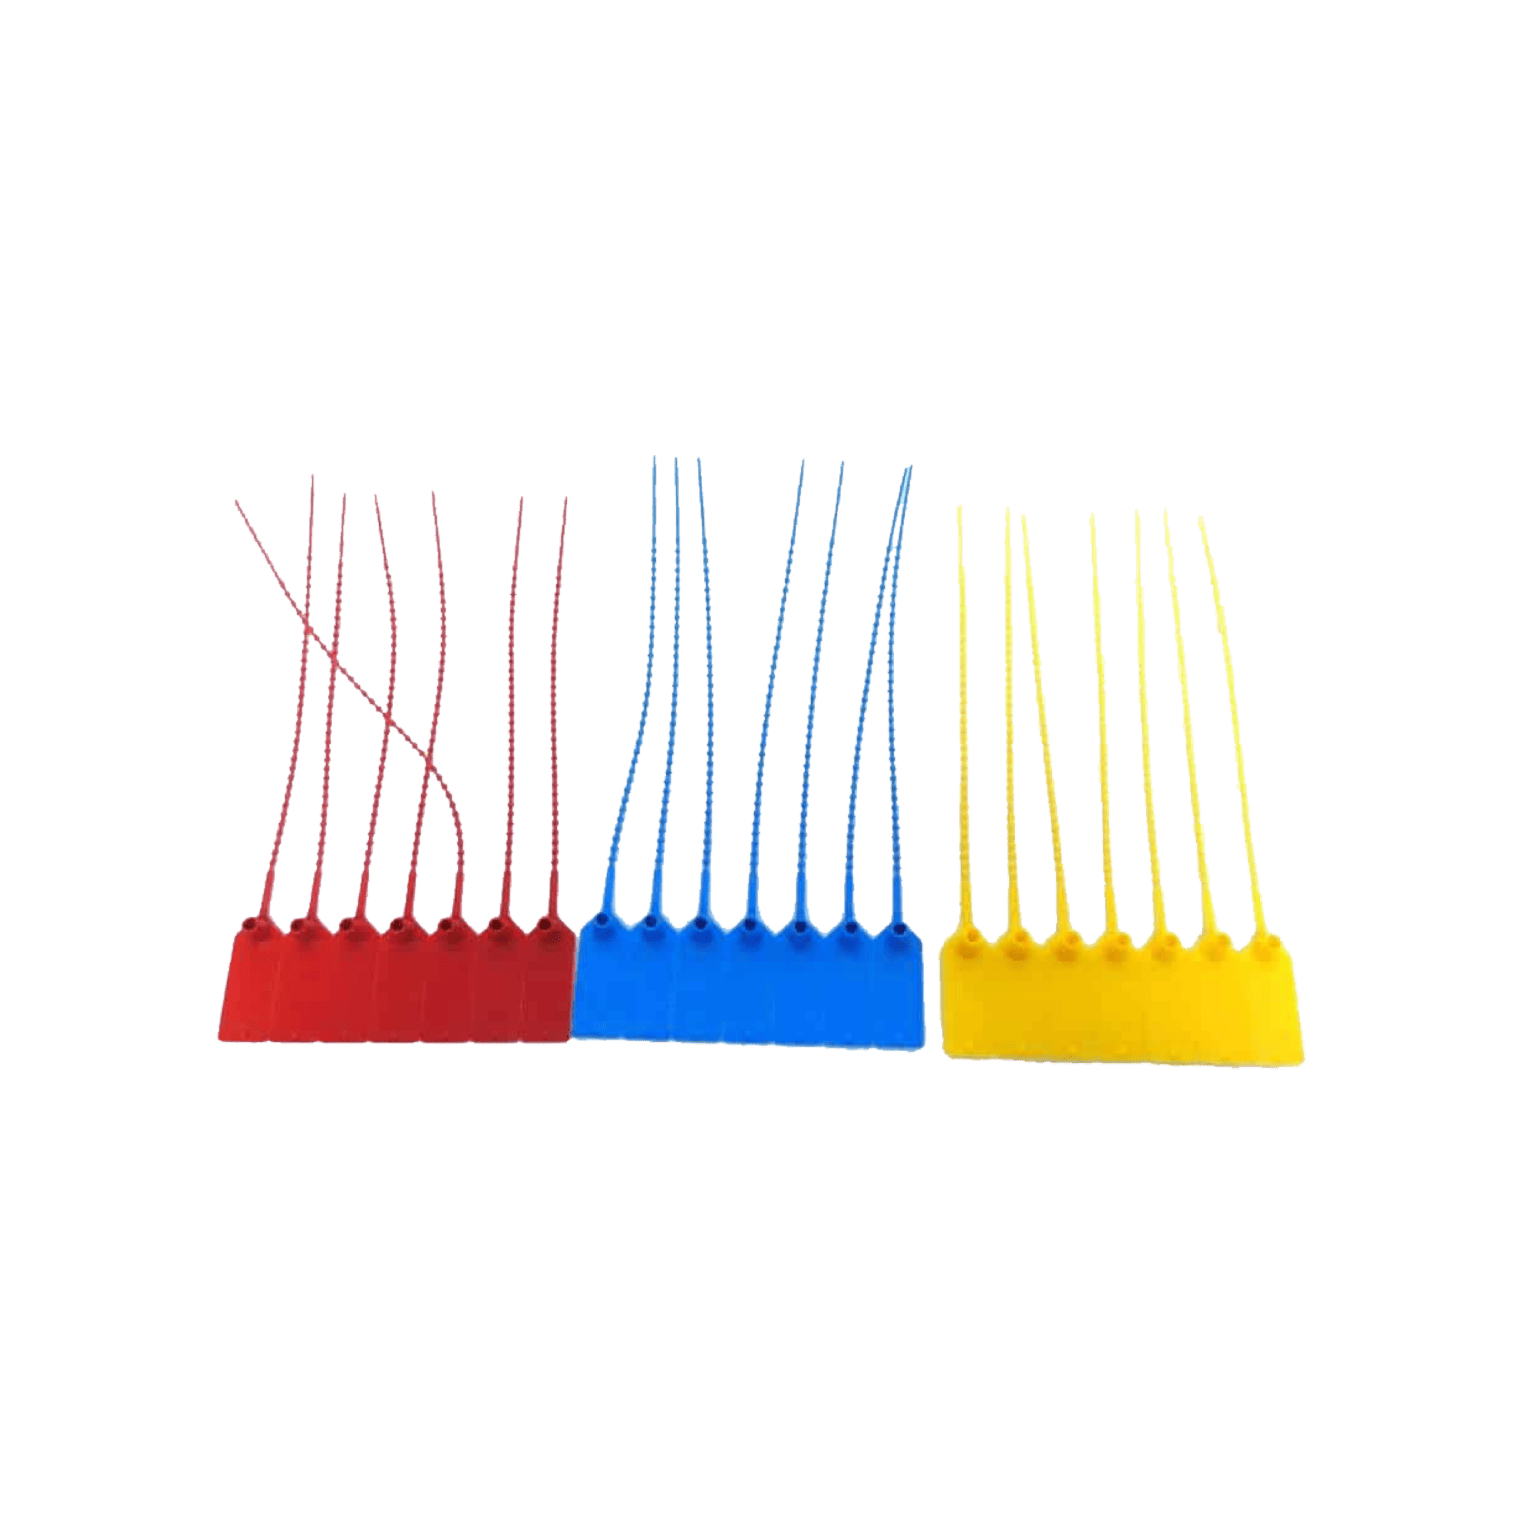

Sizes available: 0, 1, 2, 3, 4 and 5

- Each size is colour coded for ease of use.

Size 0 – 30-00222

Size 1 – 30-00223

Size 2 – 30-00224

Size 3 – 30-00225

Size 4 – 30-00226

Size 5 – 30-00227